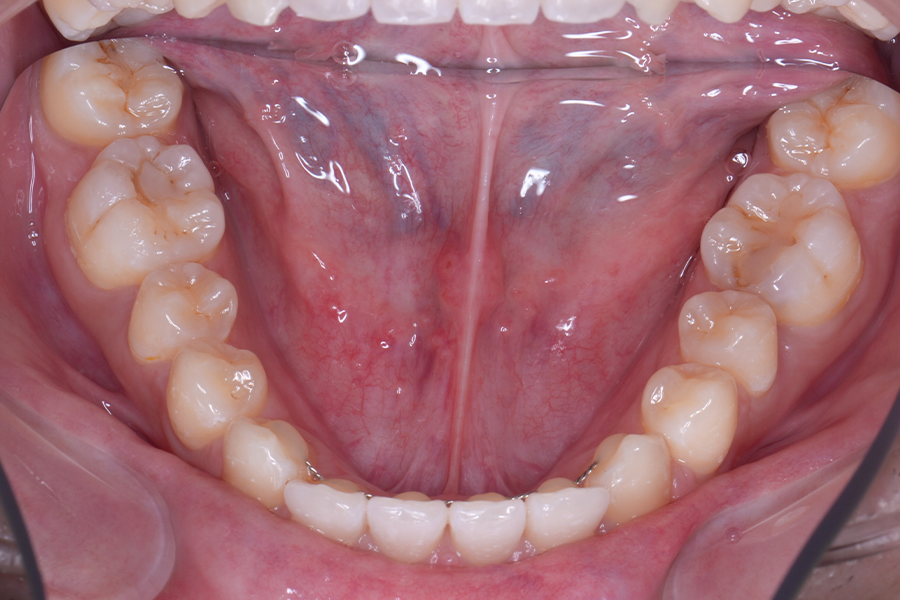

• 治療前